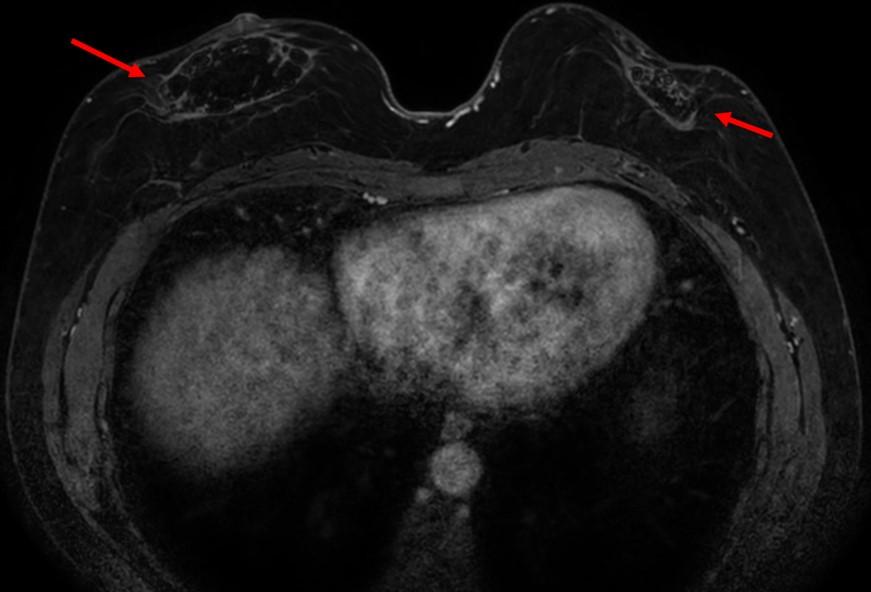

腋下MR影像显示双侧呈球形肿块,在T1WI上表现为低信号。在T1WI对比增强脂肪饱和影像中,可见腋下肿块呈异质性明显强化,伴有点状脂肪区域(图6、7)。

至今尚无研究报告显示腋窝淋巴结在自体脂肪移植(AFT)后出现脂肪浸润。然而,我们的病例通过病理学确认了这一现象。影像学发现显示这些脂肪沉积在 T1 加权 MRI 图像上表现为小的脂肪衰减区域,而在超声检查中则表现为脂肪回声。